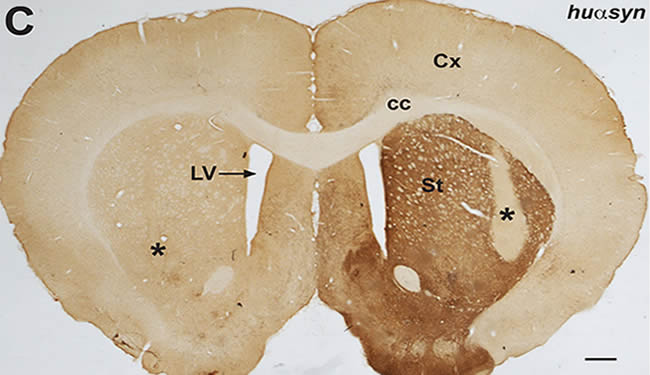

Finding Brings Scientists One Step Closer to Parkinson’s Drug

Long-term aim is to develop new treatments to block the spread of damaged proteins in the brain. Van Andel Institute...